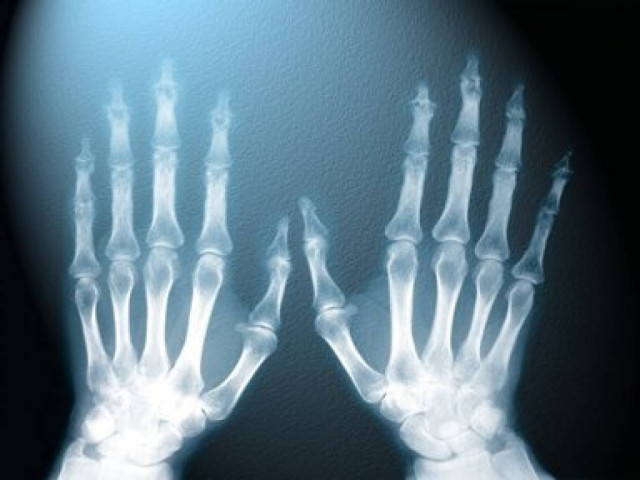

Επιστήμονες από τη Γερμανία και την Ελβετία παρουσίασαν μια καινοτομική τεχνολογία τρισδιάστατης τομογραφίας ακτινών Χ που μπορεί να εντοπίσει ακόμα και μικροσκοπικές ρωγμές ή άλλες μεταβολές στα οστά μήκους μόλις 100 νανομέτρων (δισεκατομμυριοστών του μέτρου).

Το επαναστατικό αυτό μηχάνημα δημιουργεί ακτίνες Χ από πολύ ισχυρές πηγές φωτός και ταυτόχρονα χρησιμοποιεί πολύπλοκους αλγόριθμους ηλεκτρονικών υπολογιστών για να δώσει νέα διάσταση στις δυνατότητες βιο-απεικόνισης.

Με τη χρήση της νέας τεχνολογίας, οι ερευνητές μπόρεσαν να απεικονίσουν με μεγάλη λεπτομέρεια το κάταγμα ενός οστού που ήταν μικρότερο από μια ανθρώπινη τρίχα και να «χαρτογραφήσουν» ακόμα και τις κοιλότητες των κυττάρων μέσα σε αυτό.